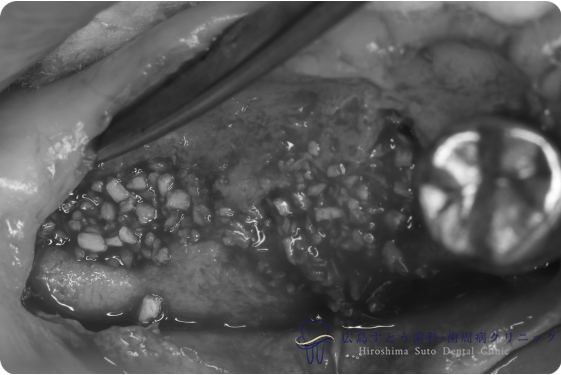

術中(手術中の写真)

手術中の状態:骨移植前

骨移植後6ヶ月

右下の手術中の状態:骨移植前

右下の手術中の状態:骨移植後